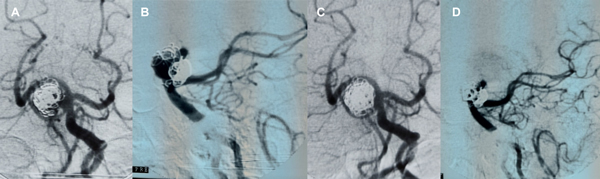

Figura 7. Paciente 17, caso 18. A- C, DSA mostrando aneurisma tipo BA- SCA izquierdo. D, inicio de coiling tras implantar Neuroform Atlas desde PComA- P1 izquierda a SCA izquierda. E- F, post embolización, RR 1. G- J, MRA control a los 3 meses.

Paciente mujer de 57 años, antecedente alejado de hemorragia intracerebral frontal derecha por ruptura de malformación arteriovenosa frontoparietal, embolizada en otro servicio y posteriormente irradiada, con oclusión parcial. Enfermedad tipo Moya Moya en territorio carotídeo derecho. Grado funcional 2 en escala de Rankin modificada. Aneurisma de cerebelosa superior izquierda con saco de 6 x 5 mm, cuello de 4.4 mm (AR 1.36, DNR 1.3) que incluye los orígenes de PCA y SCA. En consenso con la paciente y familiar se decide su tratamiento.

Con la paciente bajo antiagregación se abordan ambas arterias femorales bajo anestesia general. Tras administrar 10000 UI de heparina endovenosa, se posicionan un catéter Guider 5F en vertebral izquierda y un Guider 6F en carótida izquierda.

Desde este último se navega un microcatéter Excelsior SL 10 con extremo preformado al vapor sobre microguía Transend 0.014”, ascendiendo al sifón carotídeo hasta la comunicante posterior, con road mapping de este territorio en proyección lateral.

A continuación se utiliza road mapping de territorio vértebro- basilar en proyección anteroposterior para guiar el microcatéter sobre una microguía Hybrid 0.007” desde el segmento P1 izquierdo hacia la arteria cerebelosa superior izquierda.

Desde vertebral izquierda se accede con otro microcatéter Excelsior SL 10 con extremo preformado al vapor, hasta ubicar su extremo en la cavidad aneurismática.

Desde el primer microcatéter se implanta un stent de malla semiabierta Neuroform Atlas 3.0 x 21 mm entre la cerebelosa superior izquierda hasta el segmento P1 izquierdo, describiendo una “C” que cubre el cuello del aneurisma y protege el origen de la arteria cerebelosa, y a continuación se implantan microcoils desde el microcatéter “jailed” hasta lograr una oclusión completa, sin observarse alteraciones en la circulación cerebral.

La paciente se mantiene estable, bajo doble antiagregación, y la MRA a 3 meses confirma oclusión persistente (figura 7).